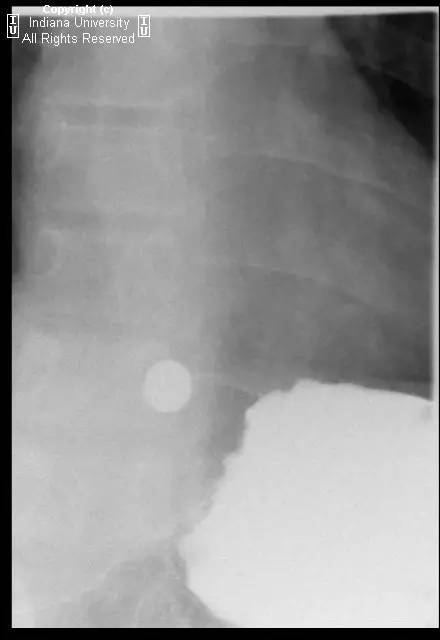

【影像学表现】可见小滑动性食管裂孔疝,食管远端胃食管连接处上方亦见一小的边界清晰的环形充盈缺损,钡剂通过顺利,但直径13mm不透射线的药片吞水后仍在充盈缺损上方崁顿,数分钟后进入胃。

【诊断】Schatzki环(舍茨基环)并滑动性食管裂孔疝

Schatzki ring andsliding hiatal hernia.